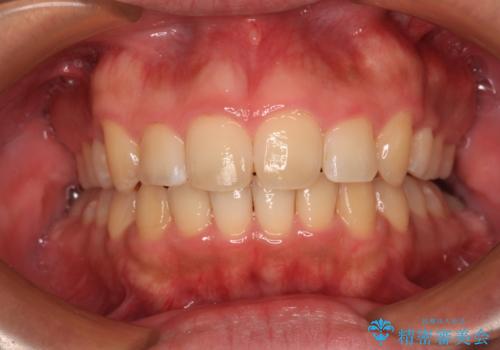

上顎歯列全体がスムーズに後方移動でき、1年で治療を終えることができました。